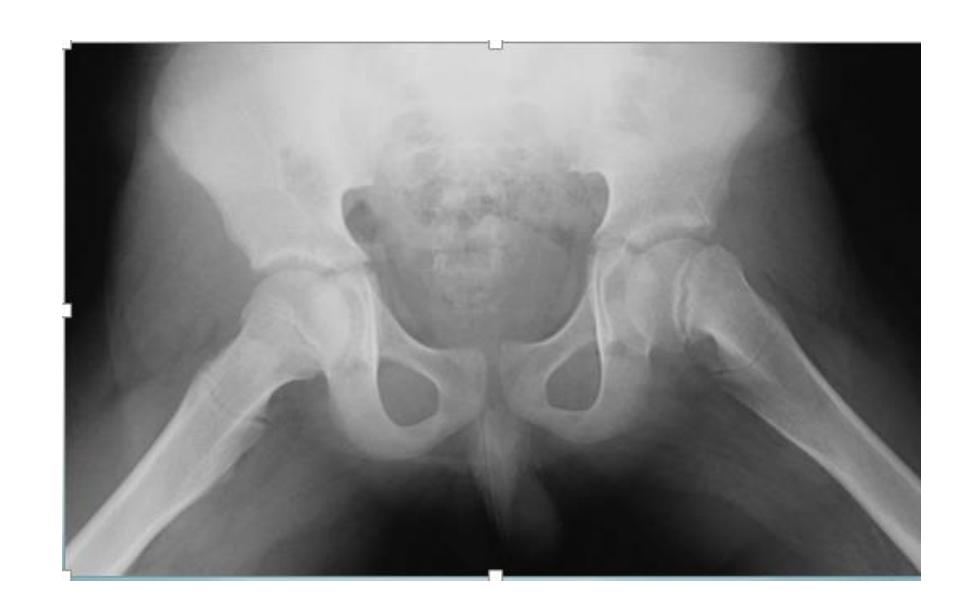

Perthes Disease (Legg-Calve-Perthes)

Clinical Presentation

Q4/ 7 years old boy, noticed by his parents that he had limping over last 3 months. x-ray obtained. Whatโs the diagnosis?

- Pertheโs disease

Diagnosis: Legg-Calve-Pertheโs Disease

- Collapse โ Fragmentation - flattening (coxa plana)

A 7 year old boy presented to emergency room with painful limping right lower limb. Clinically he has limitation of abduction and internal rotation movement at his right hip.

Q1: Mention two abnormal findings:

- Collapse and fragmentation of epiphysis

- Sclerosis

Q2: What is the most probable diagnosis?

- Legg-Calve-Pertheโs disease

X-ray findings in Perthes disease:

- Fragmentation and collapsed epiphysis

- May initially look normal in x-ray

Slipped Capital Femoral Epiphysis (SCFE)

A 13-year-old overweight boy presented to the clinic with pain in his left thigh and knee for one month. He was limping. There was no swelling and no tenderness in the thigh and knee. The hip was held in external rotation and showed limitation of internal rotation.

Q1. What is the diagnosis?

- Slipped capital femoral epiphysis (SCFE)

Q2. What is the treatment of choice?

- Fixation in situ without manipulation, and fix the other limb because there is 1/3 of cases have recurrence in the other joint

14 years old boy, limping, obese, hypogonadism

X-ray: AP and Frog lateral

Presentation: Acute: painful, Chronic: painless

Diagnosis: Slipped Capital Femoral Epiphysis (SCFE)

Signs:

- Hip externally rotates when flexed

- Limited internal rotation